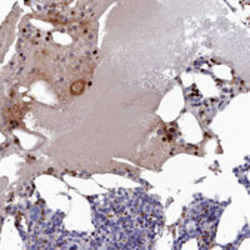

Supportive validation

- Submitted by

- Abnova Corporation (provider)

- Main image

- Experimental details

- Immunohistochemical staining of human bone marrow with COX20 polyclonal antibody (Cat # PAB28143) shows strong nuclear staining in a subset of hematopoietic cells at 1:50-1:200 dilution.

- Validation comment

- Immunohistochemistry (Formalin/PFA-fixed paraffin-embedded sections)